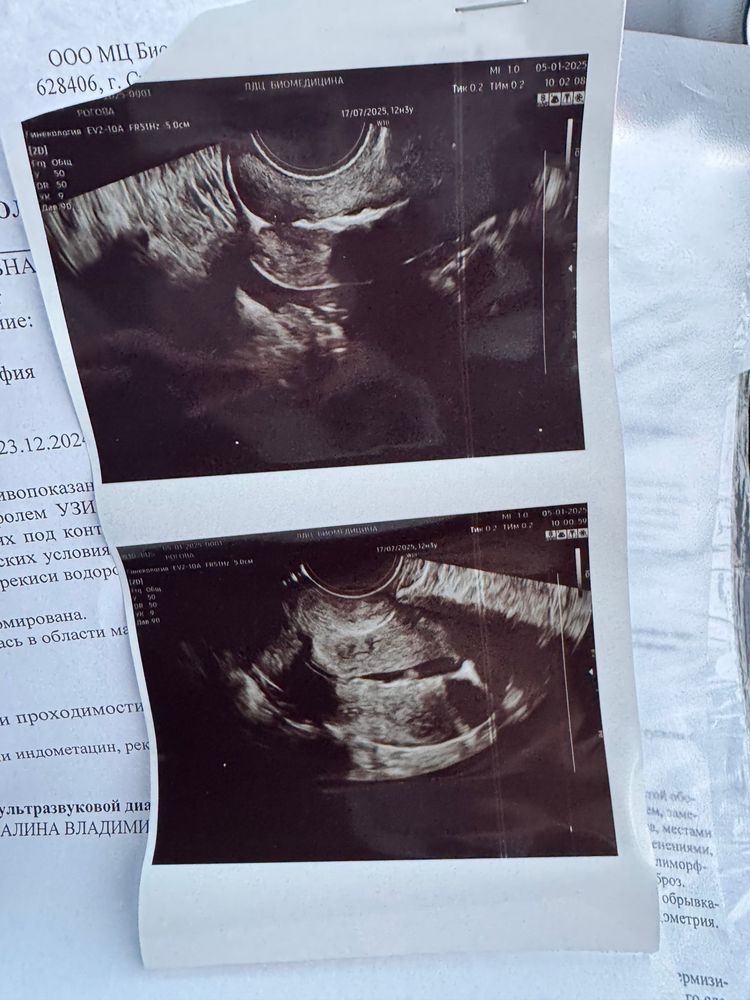

Ну вот, еще один этап перед стимуляцией пройден. Обе трубы проходимы, после введения сразу же жидкость прошла. 🥳

Я жуть как боялась самой процедуры, начитавшись отзывов. Заранее выпила 2 таблетки «но-шпа». По факту - боль была, да. Но длилась она секунд 5, при введении зонда. После - распирание при вливании жидкости. У меня сразу же пошла жидкость по трубам, поэтому много раствора не вливали. Процедура вместе с предварительным УЗИ заняла минут 10 от силы. Сразу предупредили, что сегодня может тянуть живот как на месячные и мазать немного. Прошло 2 часа с процедуры - ничего не беспокоит 🙌🏼